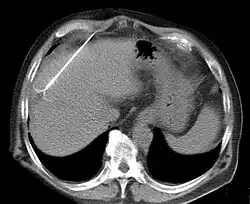

CT scan showing radiofrequency ablation of a liver lesion

RFA may be performed to treat tumors in the lung,[10][11][12] liver,[13] kidney, and bone, as well as other body organs less commonly. Once the diagnosis of tumor is confirmed, a needle-like RFA probe is placed inside the tumor. The radiofrequency waves passing through the probe increase the temperature within tumor tissue, which results in destruction of the tumor. RFA can be used with small tumors, whether these arose within the organ (primary tumors) or spread to the organ (metastases). The suitability of RFA for a particular tumor depends on multiple factors.